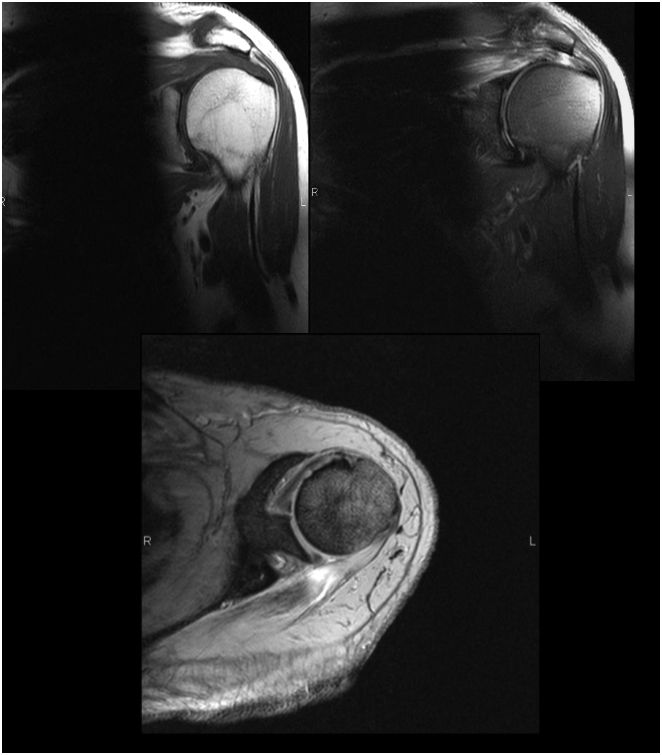

01-11-03 caso asignado (CPG ) varón de 55 años remitido por lumbociatalgia derecha , progresiva , de 4 meses de evolución .